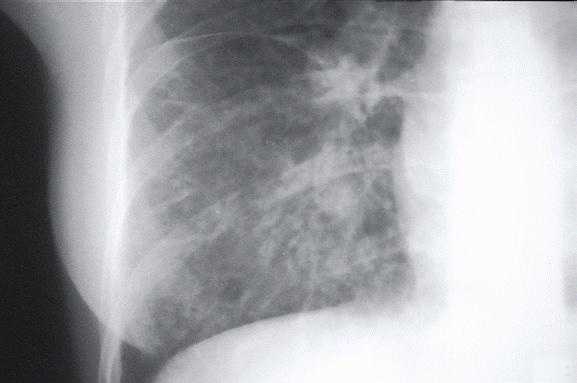

Radiologic Findings

HPS has a characteristic radiological evolution, beginning with minimal changes of interstitial pulmonary edema, progressing to alveolar edema with severe bilateral involvement. Pleural effusions are common and are often large enough to be evident radiographically. Heart size is usually normal. Cardiac silhouette size on chest radiographs is usually normal.

Approximately one-third of patients show evidence of pulmonary edema in the initial radiograph. Forty-eight hours after the initial radiograph, virtually all patients demonstrate interstitial edema and two-thirds have developed extensive bibasilar or perihilar airspace disease.

This radiograph shows the interstitial changes of early HPS. At the lung bases are Kerley B lines, short linear opacities which are perpendicular to the pleural surfaces. The longer linear opacities radiating from the lung hilum are known as Kerley A lines. Together these findings are classically seen in heart failure, but are also seen in HPS. Peribronchial cuffing is also seen well on this film. The bronchi viewed end on are surrounded by a “cuff” of edema. This makes the bronchi appear as prominent circular opacities, appearing as “ring-like” shapes next to pulmonary blood vessels.

The lack of peripheral distribution of the initial airspace disease, the prominence of interstitial edema and the presence of pleural effusions early in the disease process help distinguish HPS from ARDS. There is, however, overlap in the radiographic appearance of the two diseases. Atypical pneumonias such as that caused by mycoplasm pneumonia can produce radiographic findings similar to early HPS, although the clinical illness tends to be much less severe.